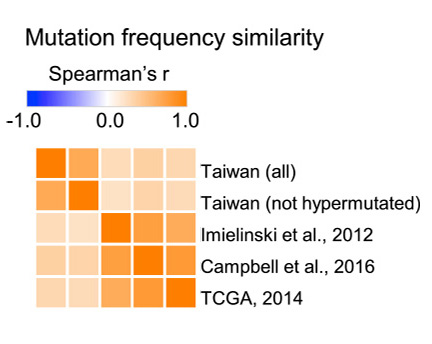

Biểu đồ liên quan đến tần suất đột biến được quan sát giữa nghiên cứu về ung thư phổi tại Đài Loan và nghiên cứu ở nước ngoài.